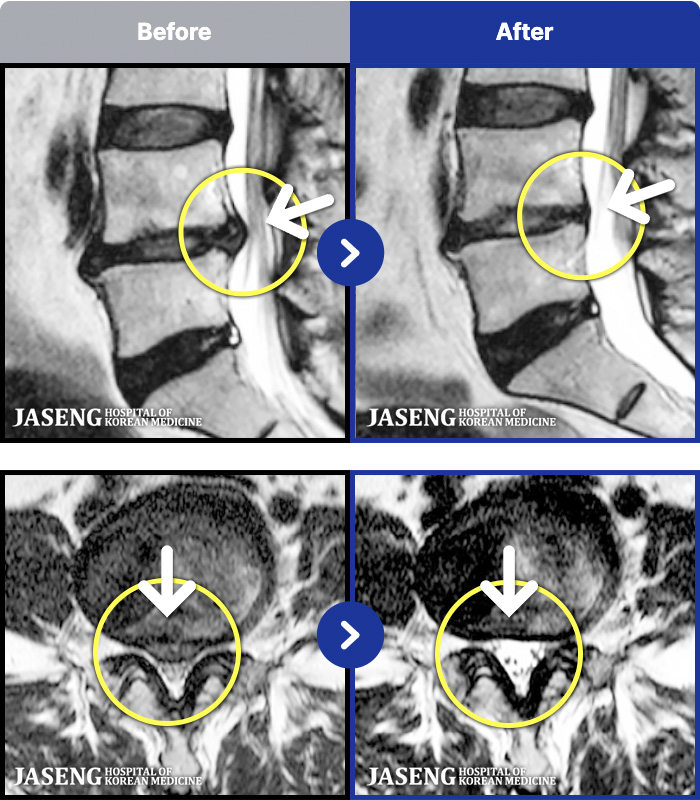

- MRI ġ

MRI ġ

1,240 MRI ũ ʸ Ȯϼ.